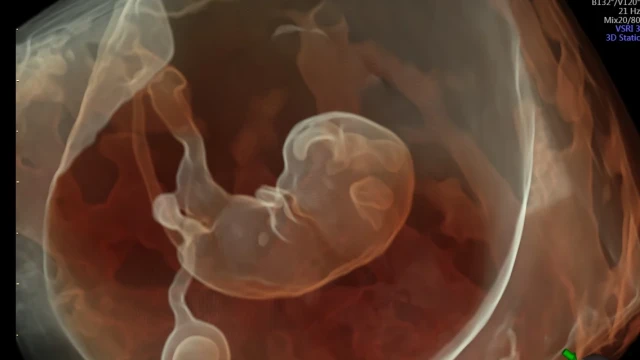

The placenta-on-a-chip model was fabricated and meticulously tested to simulate the transport of NTX/6β-naltrexol from the maternal channel to the fetal channel. From the fetal channel, the transported NTX/6β-naltrexol was collected and directed toward cultured N27 neural cells. The neural cells were then evaluated for gene expression and cell viability following exposure to the pharmaceutical agents.

The placenta-on-a-chip microsystems have potential in transforming our understanding of how pharmaceutical agents affect fetal development. This technology can provide insights into the complex processes that occur during pregnancy, ensuring safer and more informed medical practices.